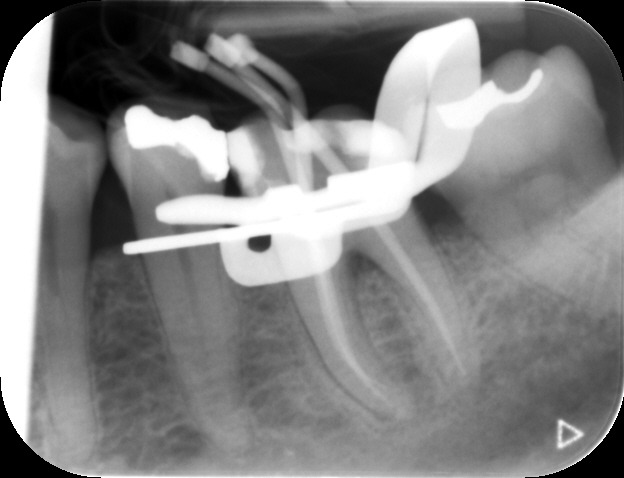

Before commencing the treatment, a local anaesthetic is administered and later a protective non-latex rubber sheet is placed around the tooth to prevent saliva contaminating the tooth and at the same time improves patients comfort.

An access cavity is placed on the surface where the patient bites, to reach the root canals of the tooth. Once all the canals are identified, small files are used to remove the infected pulp.